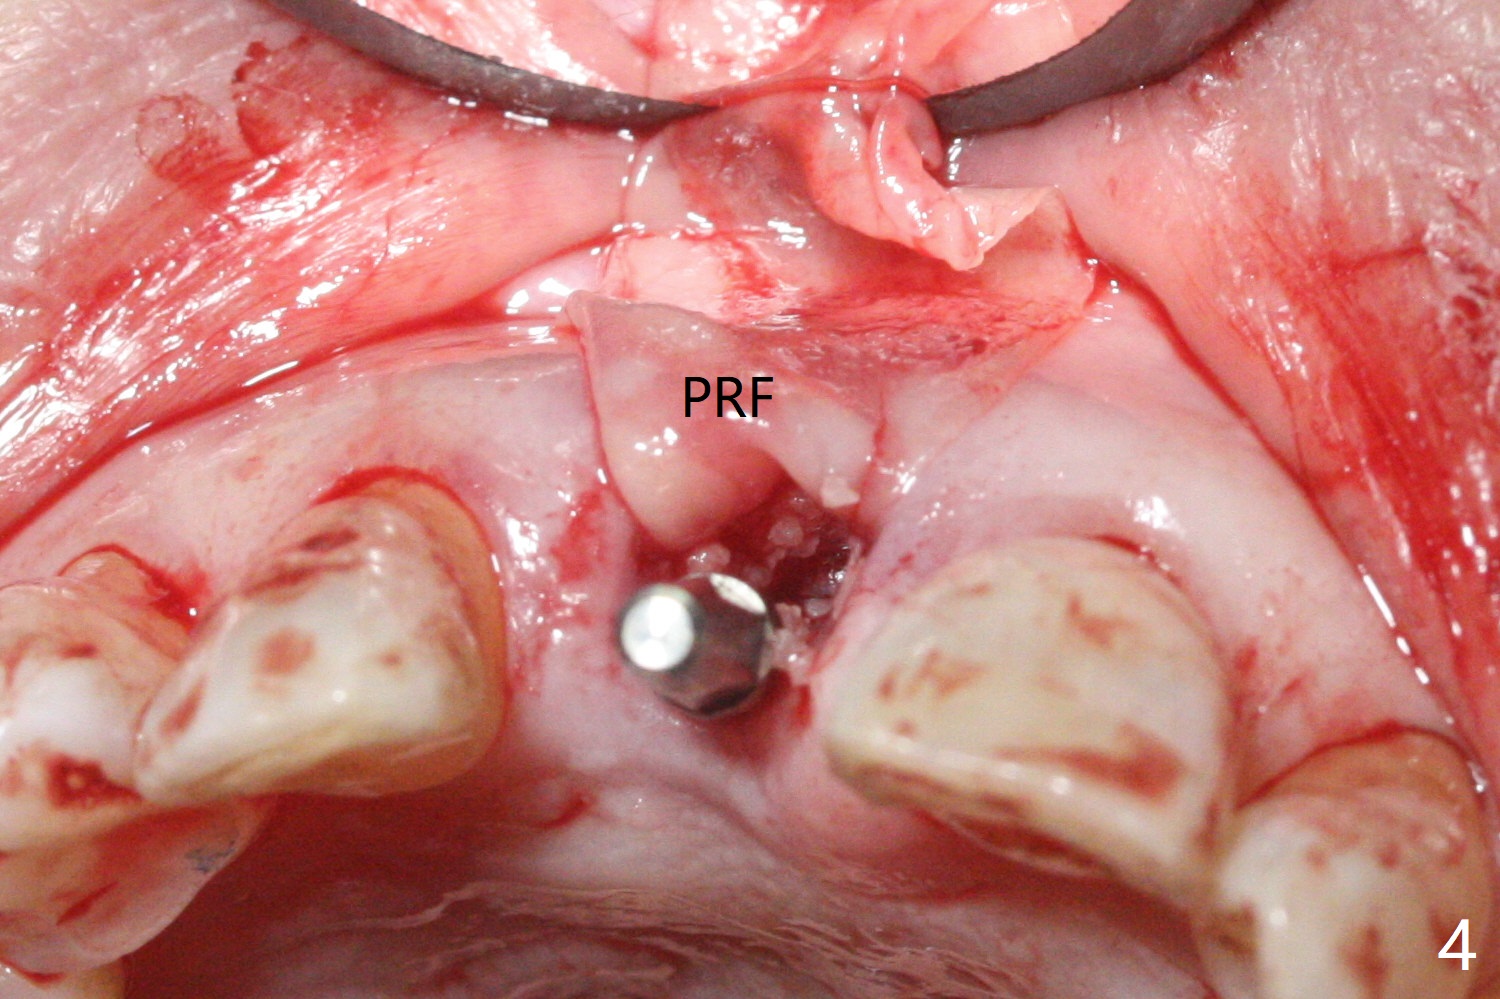

59岁女术前右下1,2切缘磨短后,右上1颊侧移位得到纠正(图一(咬合创伤))。拔牙后证实颊侧骨板缺失,钻洞始于腭侧(图二),当1.5毫米钻头感觉刚穿破鼻底时,置入2.5x14(4)毫米一段式植体,好像进入鼻腔,但是扭力<10Ncm(图三)。把一张PRF膜放入牙槽窝,一端紧贴颊侧牙龈腭侧,另一端放置颊侧牙龈颊侧(图四),然后开始用粘性骨粉(图五,七:*(100%皮质骨))充填颊侧间隙。后者填满时(图五:*),将外面一端PRF翻转覆盖牙槽窝开口,并插入基台固定(图六),最后插入龈下,用临时牙冠固定(图八(T),九(*:PRF))。术后九天牙龈退缩(图十:^),临时牙冠突出(*),后者龈缘和切缘进行调整,缩短(图十一,十二),少许骨粉暴露(图十二:>),十四天后牙龈往下生长,好像形成角化龈(图十三:*)。